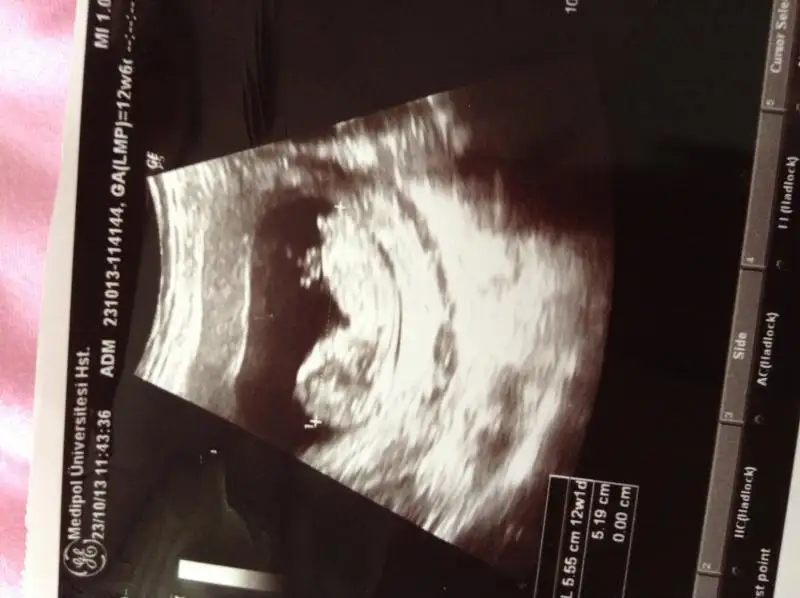

Benim gordugum 2side kiz gibi tatlimm..Eki Görüntüle 861357 12 hafta 3 günlük

bebeklerin cinsiyeti nedir acaba? biri yengemin biri benim